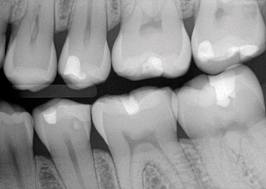

Si las radiografías están disponibles, el primer paso es clasificar las lesiones de caries coronal en dientes posteriores de acuerdo con los grados que están en la Tabla 4.

Sistema radiográfico ICDAS  (Radiografía Bite-Wing)

Sano

R0 No hay radiolucidez

Estadios iniciales *

RA1 Radiolucidez en 1/2 externa del esmalte

RA2

Radiolucidez en la 1/2 interna del esmalte ± UAD (Unión amelo-dentinaria)

Se lo considera aún un estadio inicial porque no hay dentina infectada )

RA3 Radiolucidez limitada al 1/3 externo de la dentina

Estadio moderado

(En este estadió comiemza la infección de la dentina por bacterias orales)

RB4 Radiolucidez que alcanza hasta el 1/3 medio de la dentina

Estadios severos

(Infección franca de la dentina)

RC5 Radiolucidez que alcanza hasta el 1/3 interno de la dentina, clínicamente cavitada

RC6 Radiolucidez en la pulpa, clínicamente cavitada

* Nota- La mayoría de lesiones confinadas al esmalte no se ven en las radiografías.

Tabla 4: Clasificación radiográfica ICDAS